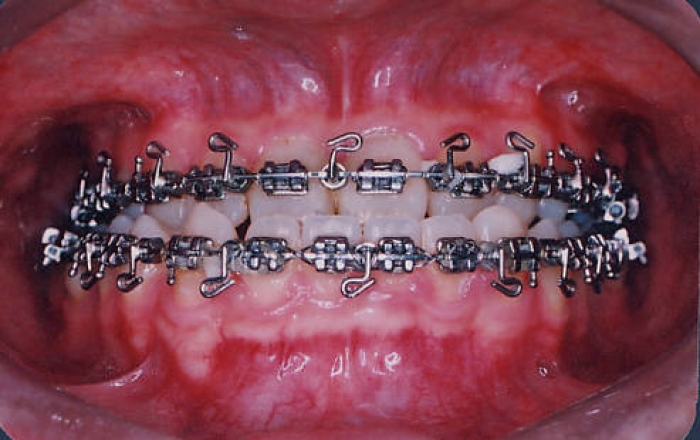

Mordida inicial

Mordida após a cirurgia